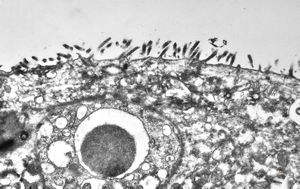

celiakia … reduced microvilli, lipid droplets